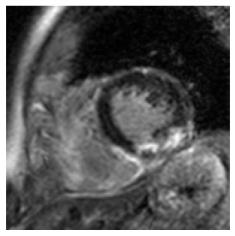

Although supervised deep-learning has achieved promising performance in medical image segmentation, many methods cannot generalize well on unseen data, limiting their real-world applicability. To address this problem, we propose a deep learning-based Bayesian framework, which jointly models image and label statistics, utilizing the domain-irrelevant contour of a medical image for segmentation. Specifically, we first decompose an image into components of contour and basis. Then, we model the expected label as a variable only related to the contour. Finally, we develop a variational Bayesian framework to infer the posterior distributions of these variables, including the contour, the basis, and the label. The framework is implemented with neural networks, thus is referred to as deep Bayesian segmentation. Results on the task of cross-sequence cardiac MRI segmentation show that our method set a new state of the art for model generalizability. Particularly, the BayeSeg model trained with LGE MRI generalized well on T2 images and outperformed other models with great margins, i.e., over 0.47 in terms of average Dice. Our code is available at https://zmiclab.github.io/projects.html.